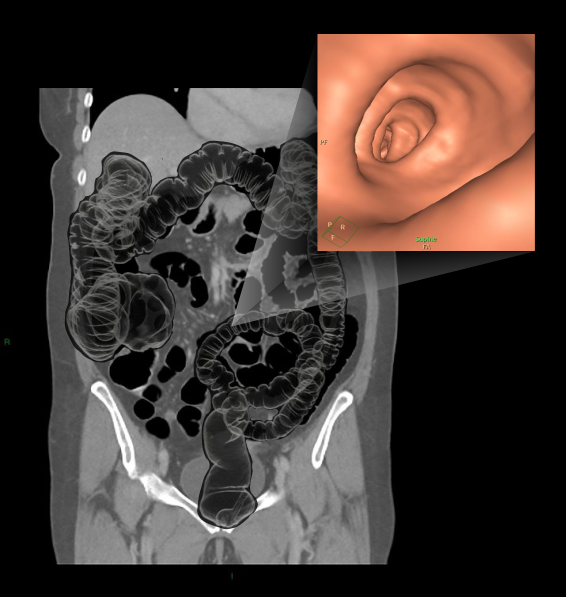

- Turn in to supine position after achieving a full colon distension, and perform a scout view toconfirm.

Post-processing

- MPR (axial, sagittal and coronal) views in soft-tissue window with 2mm slice thickness and 2mm gap for all patient positions (supine, prone and post contrast phases).

- 3D endoluminal fly-through view.

- Alternative 3D display views such as virtual dissection.